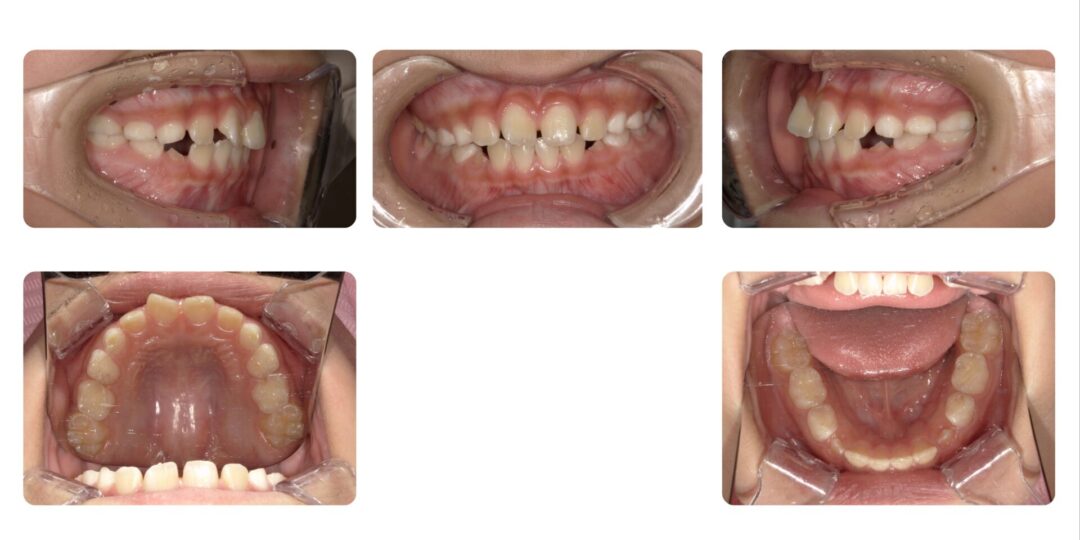

矯正治療後

第一期治療 上下拡大床による歯列矯正

治療期間

1年2ヶ月